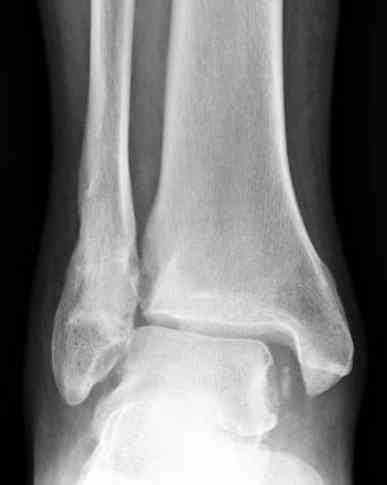

Мне кажется есть все основания попытаться сделать остеосинтез. Боль вследствие нестабильности. Нестабильность вследствие неанатомичного положения дистального отломка малоберцовой кости. Через 1,5 вполне возможно разобщить, репонировать и фиксировать длинный косой перелом наружной лодыжки. Вероятно, одновременно придется делать медиальный доступ для мобилизации внутренней лодыжки. Мы оперируем таких пациентов, функциональные (объем движений) результаты конечно хуже по сравнению с теми кого оперируем в первые 5-10 дней, но вполне удовлетворительные.

Согласен, на предоставленных рентгенограммах все основания для проведения открытого остеосинтеза.

сроки действительно небольшие, но если мы его и возьмем, то пройдет еще минимум неделя, кроме того смущает впечатление сращения н/лодыжки, похоже, что придется не разобщать,а остеотомировать, формирование оссификатов в полости сустава с медиальной стороны, да и сам пациент 1,5 месяца по поводу своей травмы сильно не напрягался

Здравствуйте, Максим! Мое мнение - оперировать, вот только срок после травмы определяет последовательность оперативных действий. В свежем случае при таком повреждении операция начинается с репозиции и синтеза наружной лодыжки, затем - вмешательство на внутренней стороне. В данном случае ригидность тканей может не позволить Вам, начав операцию снаружи, произвести адекватную репозицию. Мы в таких случаях поступаем следующим образом: начинаем с внутреннего доступа, из которого производим мобилизацию внутренней лодыжки. Затем из наружного доступа выполняем мобилизацию перелома наружной лодыжки. После этого достигается мобильность, характерная для свежего перелома. Синтез производим в последовательности: наружная сторона, синдесмоз (при необходимости), внутренняя сторона. 6 недель - не критический срок. Удавалось восстановить повреждения 3-4 месячной давности с хорошими функциональными результатами. А почему больных с такими сроками после травмы очень много - совсем другой вопрос. Кстати, почти наверняка сращения еще нет. Удачи! Константин Деданов, Челябинск, Областная больница